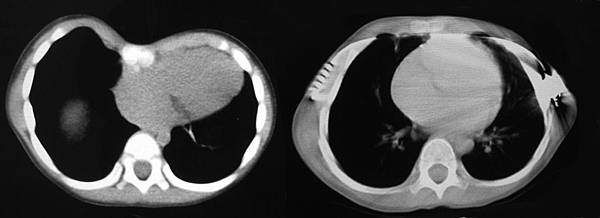

手術前後心臟被壓迫情況的攺善影像

凹胸最常見的問題,除了外觀外, 就是心臟的壓迫了, 胸腔的空間縮小, 心臟受到擠壓, 除了變形外, 也常被推入左側胸腔, 壓迫肺臟.

尤其是心臟三尖瓣逆流, 二尖瓣脫垂, 肺動脈高壓, 心搏出功率減少等等, 均常會因漏斗胸的壓迫而發生, 在手術後大多會有明顯改善.

手術前應要仔細評估心肺功能及壓迫情形. 下列三圖, 左側為矯治前, 右側為矯治後.